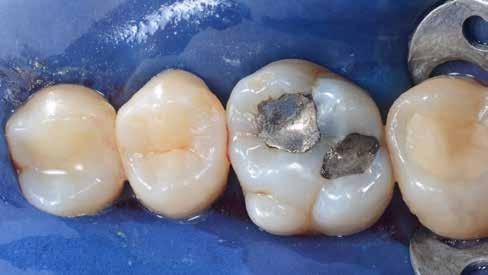

2. ábra: A páciens egy nem megfelelő I. osztályú ezüstamalgám töméssel és II. osztályú szuvasodással jelentkezett. A fog izolálása kofferdám alkalmazásával történt.

3. ábra: A preparálás, a bondozás és a kompozit felvitele után. (Megjegyzés: némi kompozit túlfolyás látható a mesiális doboz axiális falain).